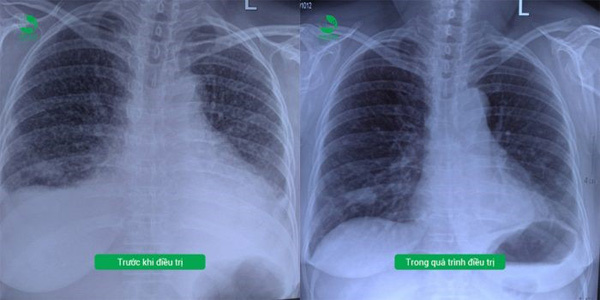

Sau một thời gian điều trị, sức khỏe cô S đã ổn định và bắt đầu truyền hóa chất theo phác đồ đã được chỉ định. Sau 2 tháng, từ việc gắn liền với giường bệnh và máy thở, cô đã khỏe mạnh, tự ăn uống và sinh hoạt bình thường. Hiện tại, cứ 3 tuần 1 lần, cô S lại đến bệnh viện để truyền hóa chất.

| Tình trạng bệnh cải thiện trong quá trình điều trị |